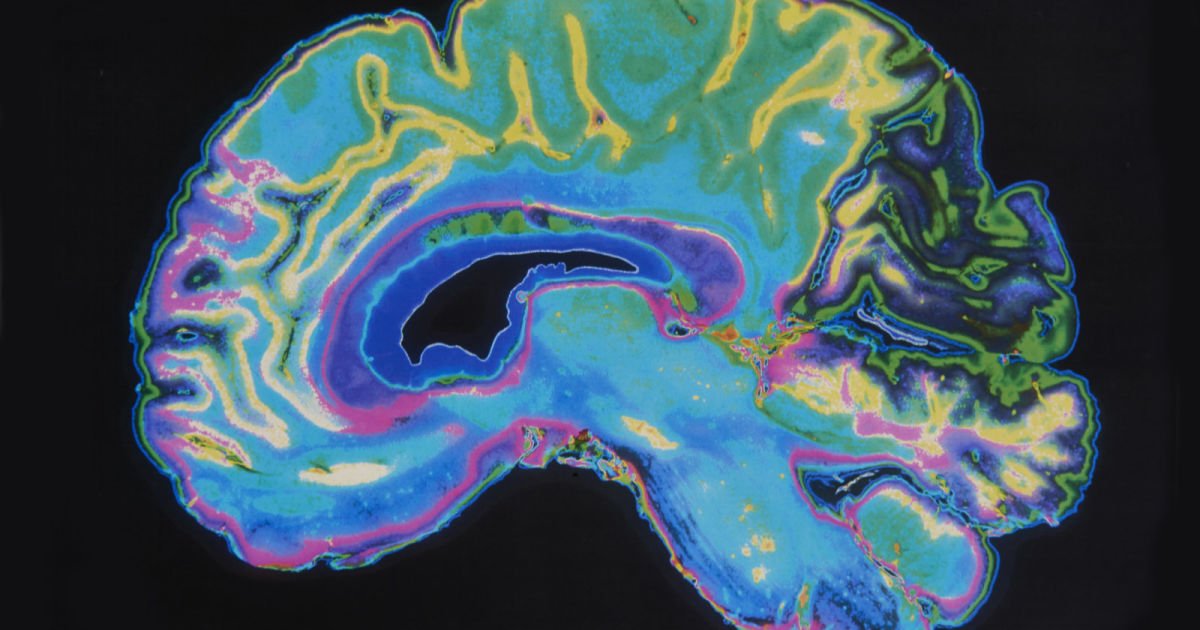

Learn how

#IBMResearch &@UofAResearch are using#AI and#MachineLearning to help predict schizophrenia http://ibm.biz/BdiWjD@AmiiThinkspic.twitter.com/5ffgAT6gFzಧನ್ಯವಾದಗಳು. Twitter ಇದನ್ನು ನಿಮ್ಮ ಕಾಲರೇಖೆಯನ್ನು ಉತ್ತಮಗೊಳಿಸಲು ಬಳಸುತ್ತದೆ. ರದ್ದುಗೊಳಿಸು -

IBM Research ಅವರು ಮರುಟ್ವೀಟಿಸಿದ್ದಾರೆ

IBM's AI can predict schizophrenia by looking at the brain's blood flow http://engt.co/2udVUZL pic.twitter.com/RE37lHNbCH